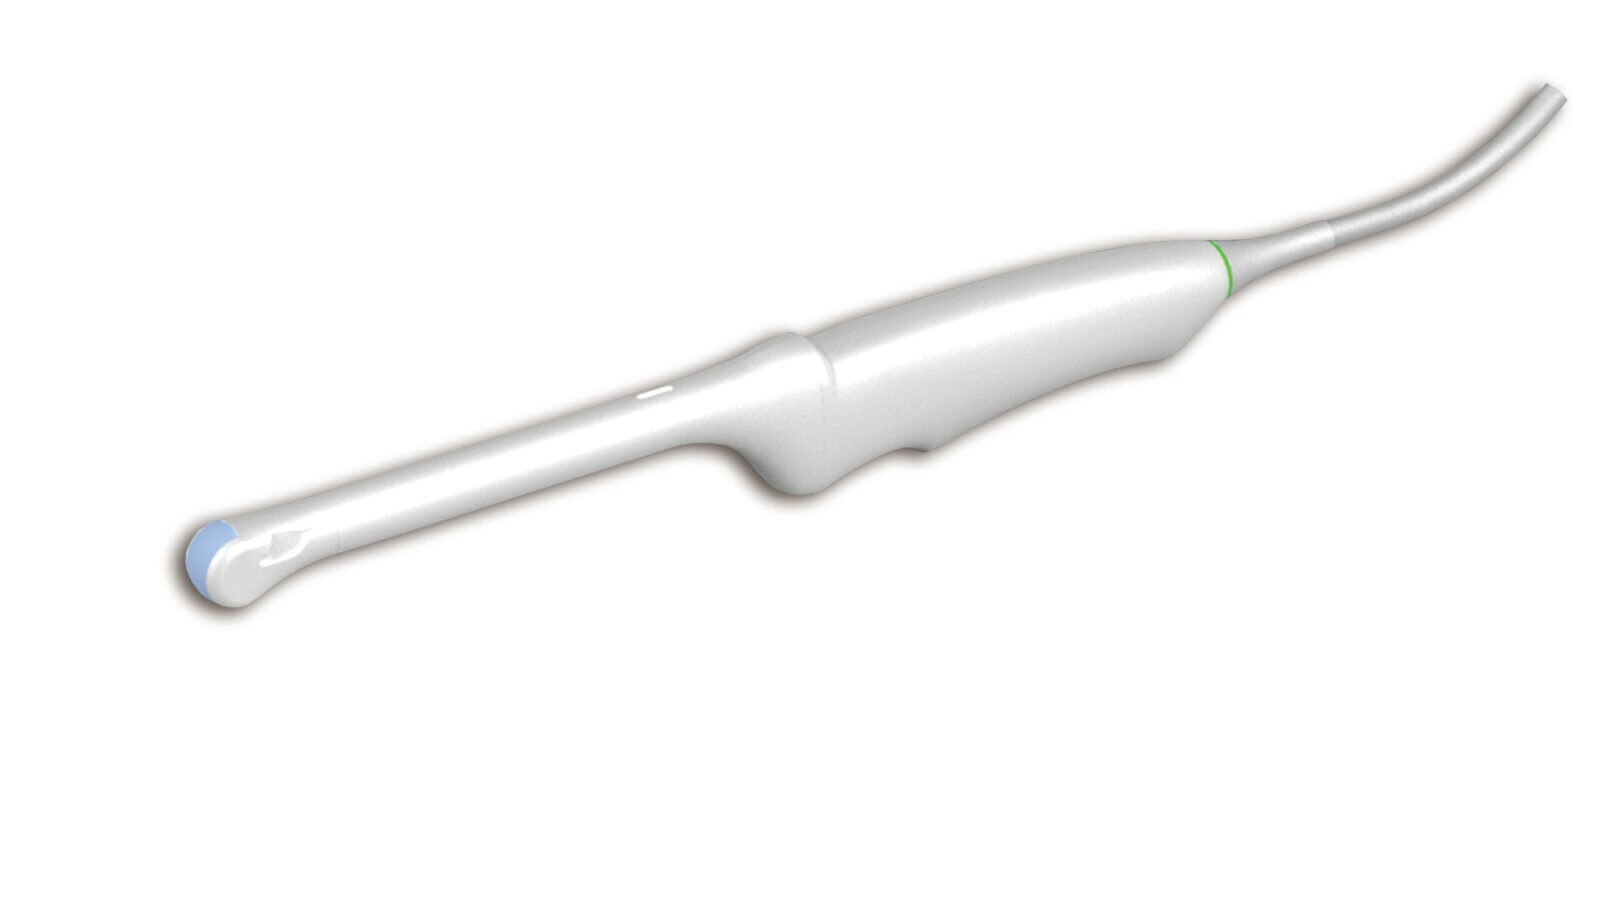

Внутриполостной E8-4QL17-7Q

Внутриполостной E8-4Q

Трансвагинальный E8-4D

Трансвагинальный E612UB